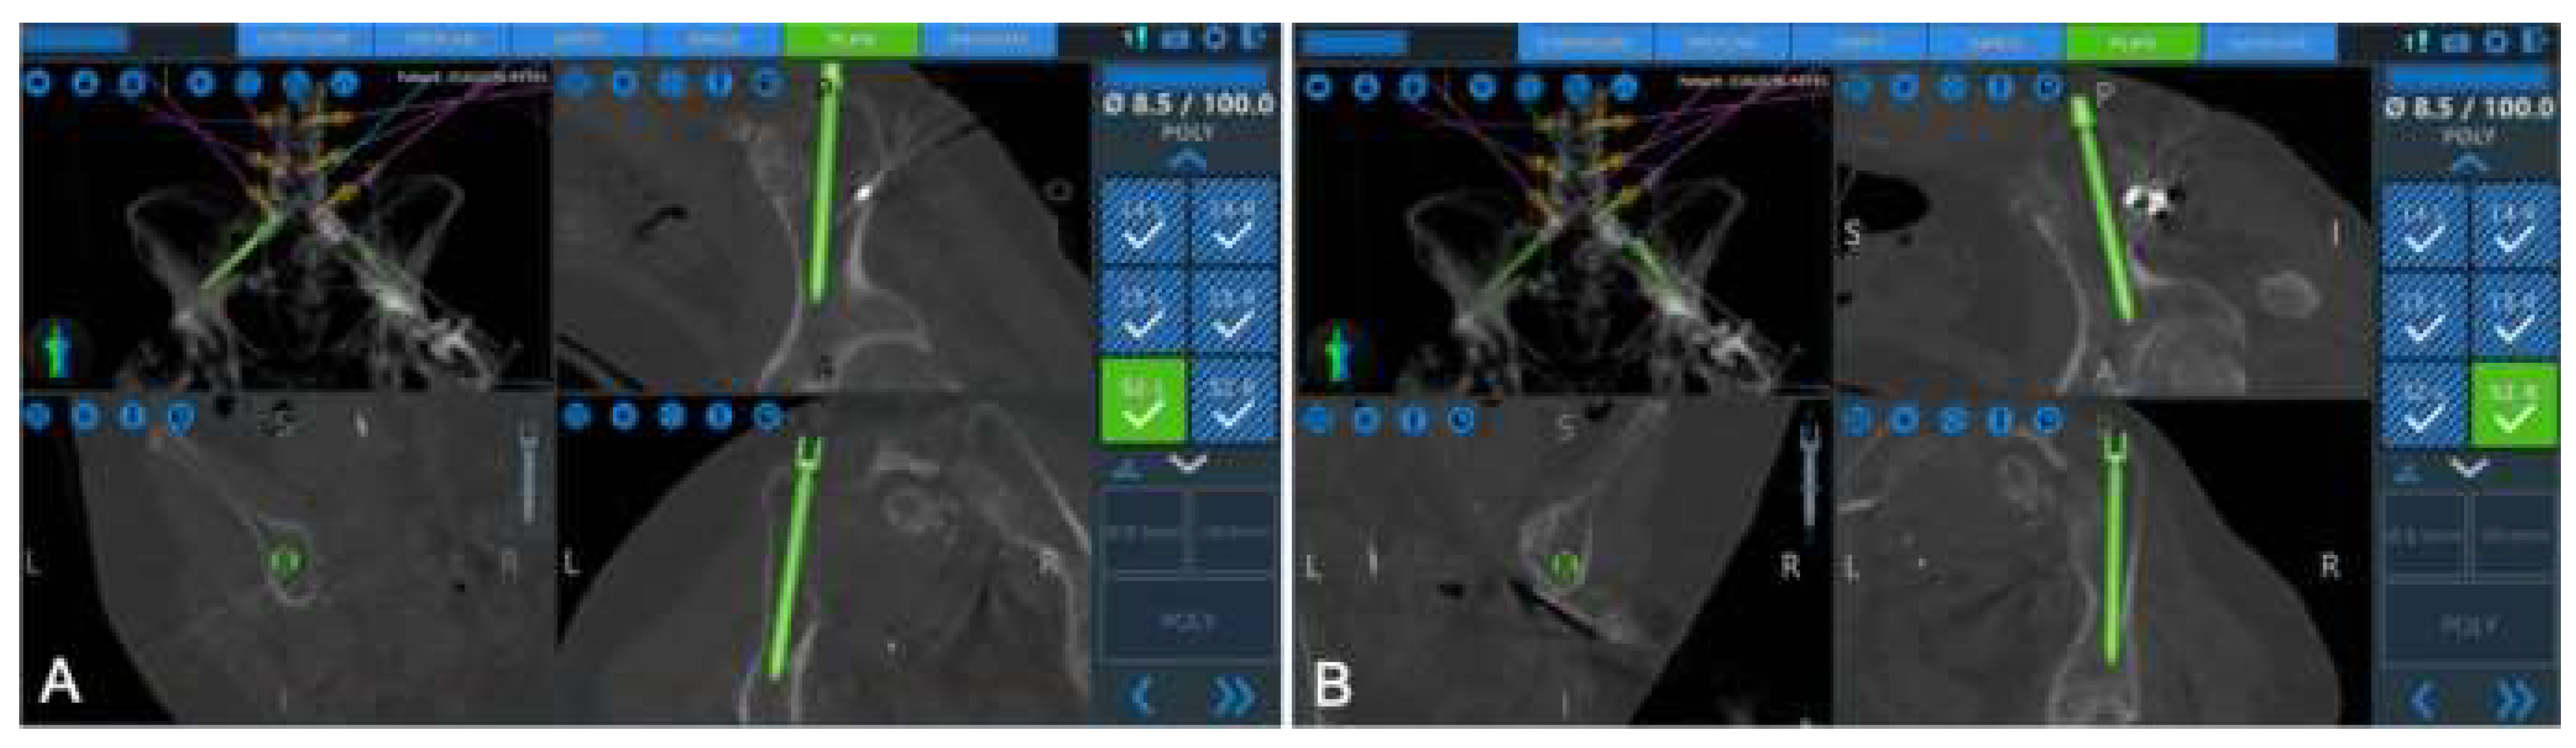

- Tabarestani, T.Q.; Salven, D.S.; Sykes, D.A.W.; Bardeesi, A.M.; Bartlett, A.M.; Wang, T.Y.; Paturu, M.R.; Dibble, C.F.; Shaffrey, C.I.; Ray, W.Z.; et al. Using Novel Segmentation Technology to Define Safe Corridors for Minimally Invasive Posterior Lumbar Interbody Fusion. Oper. Neurosurg. 2023. [Google Scholar] [CrossRef] [PubMed]